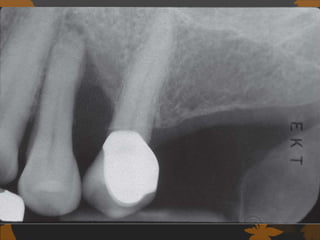

IMPLANT PLACEMENT CONSIDERATION

 Diabetes-induced changes in bone formation:

 Inhibition of collagen matrix formation

 Alterations in protein synthesis

 Increased time for mineralization of osteoid

 Reduced bone turnover

 Decreased number of osteoblasts and

osteoclasts

 Altered bone metabolism

 Reduction in osteocalcin production

 Possible Diabetic Disturbances in Implant Wound

Healing Process In Implants